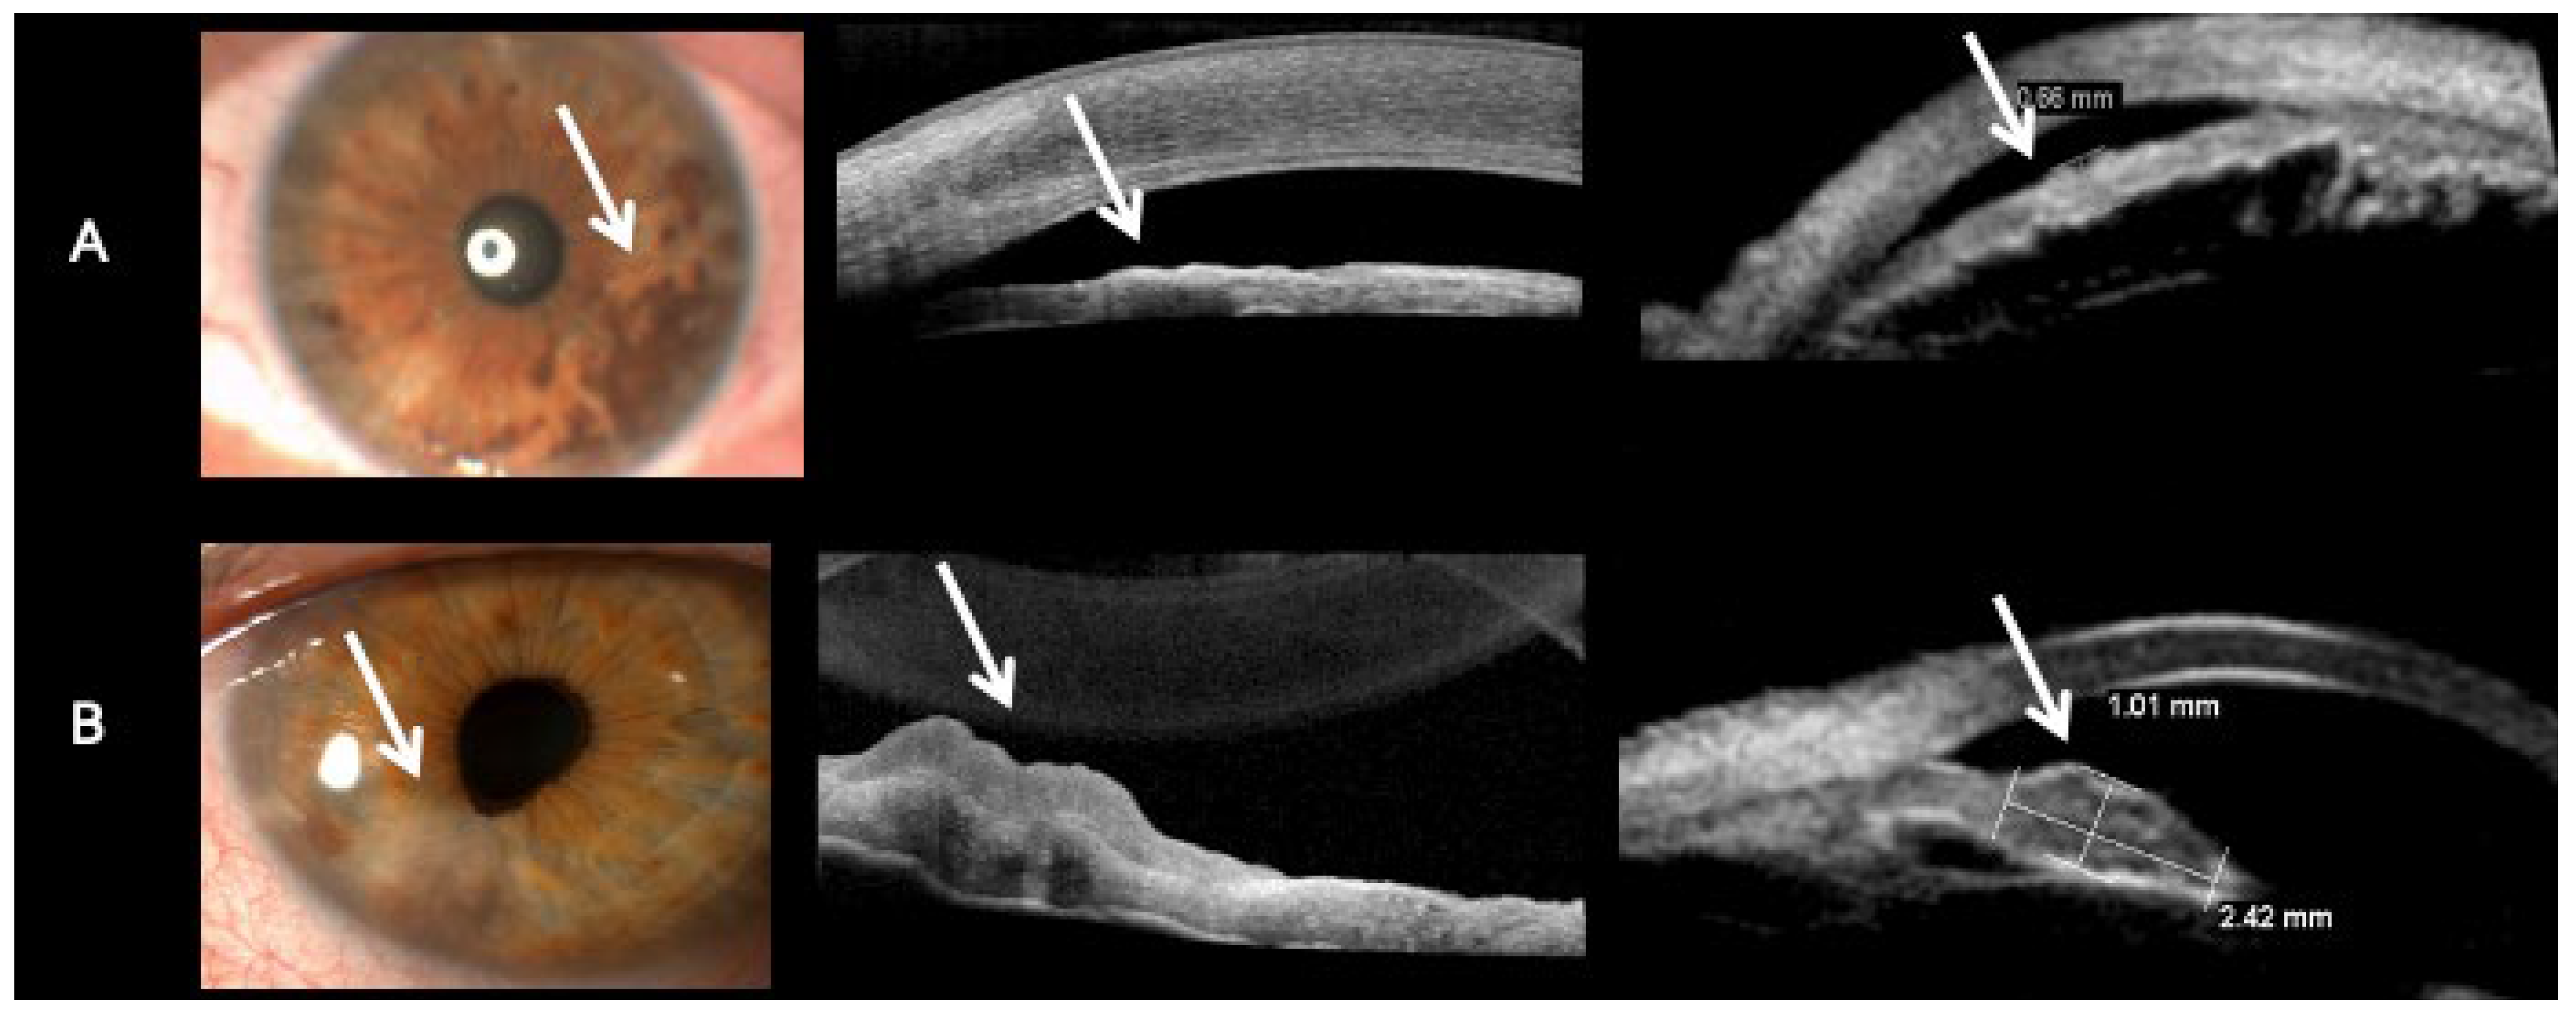

| Evaluation of Iris Melanoma with Anterior Segment Optical Coherence Tomography | Eren et al. | 2018 | [27] | Amelanotic lesions showed reflectivity equal to or lower than iris stroma; heterogeneous internal structure. | Low-to-moderate reflectivity, independent of pigmentation; clear posterior margin visualization. |

| Imaging of Anterior Segment Tumors: A Comparison of Ultrasound Biomicroscopy Versus Anterior Segment Optical Coherence Tomography | Kottaridou et al. | 2024 | [29] | Amelanotic lesions depicted with low to moderate reflectivity, distinct from highly reflective melanotic lesions. | Better visualization of all tumour margins and posterior surfaces; complete penetration of lesions. |